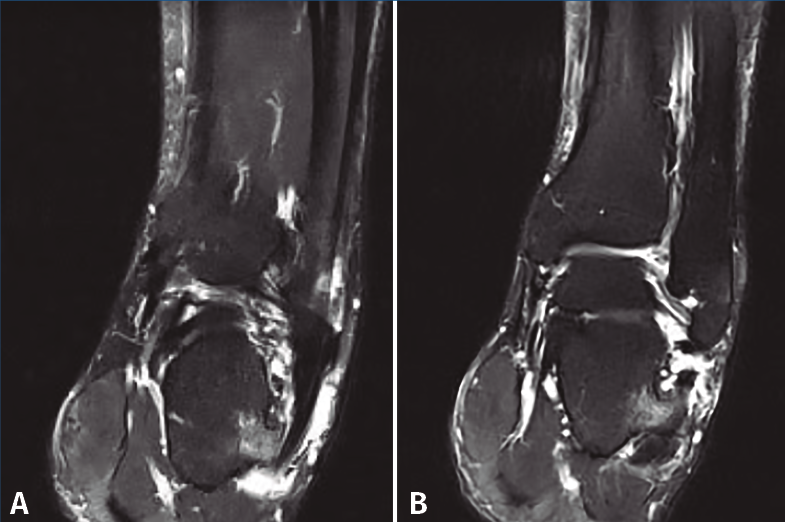

Se realizan los estudios complementarios mediante radiografías, en las que se observa una lesión ósea en la cara lateral del calcáneo con bordes irregulares (Figura 2). La resonancia magnética nuclear informa de “hipertrofia del tubérculo lateral del calcáneo que conlleva severa afectación de los tendones peroneos apreciando signos de tenosinovitis y afectación mayor del tendón peroneo lateral largo con rotura parcial del mismo” (Figuras 3A y 3B). La tomografía computarizada muestra una “exóstosis en cara externa de calcáneo de 12 × 9 × 8 mm” (Figuras 4A y 4B).

Figura 3. Imágenes de resonancia magnética nuclear donde podemos ver la tumoración con edema óseo asociado y tenosinovitis de los tendones peroneos.